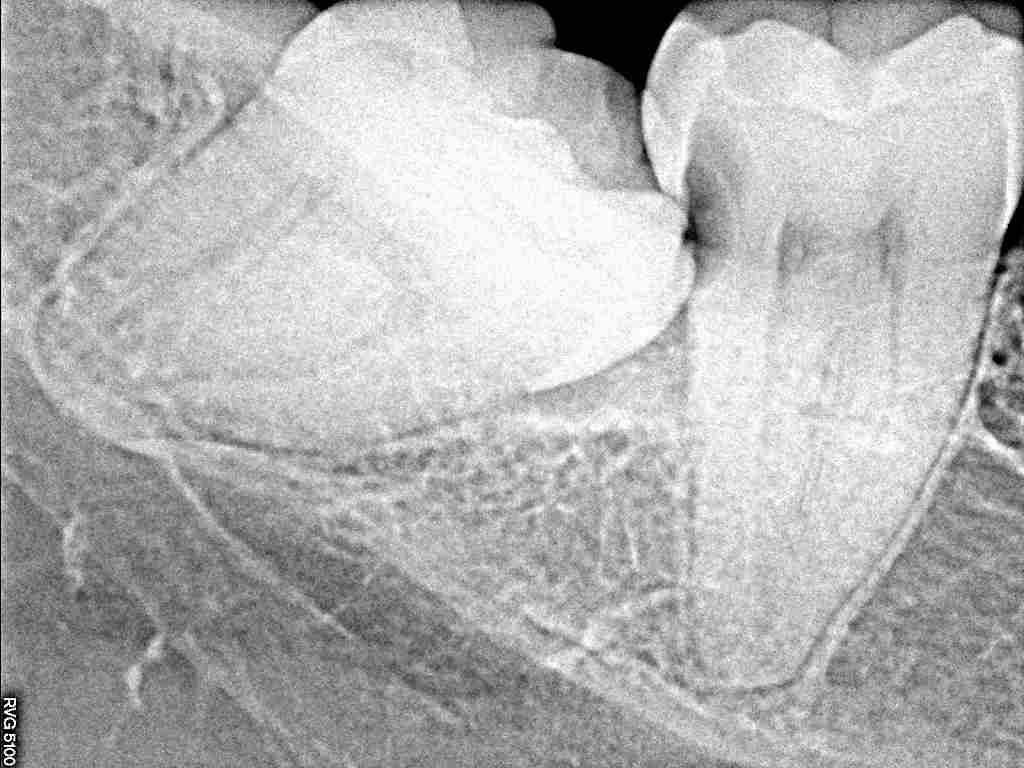

右下の親不知難抜歯。 一つ手前の歯も虫歯を作るようになります。| |広島市安佐南区の歯科医院 右下の親不知難抜歯。 一つ手前の歯も虫歯を作るようになります。 トップ お知らせ・ブログ 右下の親不知難抜歯。 一つ手前の歯も虫歯を作るようになります。 右下の親不知難抜歯。 一つ手前の歯も虫歯を作るようになります。 Web診療予約 初めての方へ 選ばれ続ける理由 院内設備について 歯が痛いしみる一般歯科 歯がぐらぐらする歯周病 健康な歯を保ちたい予防歯科 子供の虫歯予防をしたい小児歯科 銀歯をセラミックに審美歯科 白い歯を目指しませんか?ホワイトニング 矯正専門医がいるので安心矯正歯科 抜けた歯を補いたいインプラント・入れ歯 医院案内 スタッフ紹介 メリィハウス歯科クリニックオフィシャルホームページ ラベンダー歯科クリニックオフィシャルホームページ お知らせ・ブログ ホーム 診療科目 一般歯科 歯周病治療 予防治療 小児歯科 審美治療 ホワイトニング 矯正歯科 入れ歯・インプラント マウスピース矯正 初めての方へ 院長・スタッフ 設備紹介 医院案内・アクセス メニューを閉じる